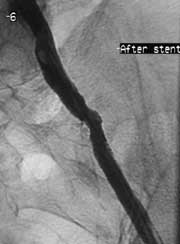

Увеличить

Рис. 6. Контрольная артериограмма после стентирования.